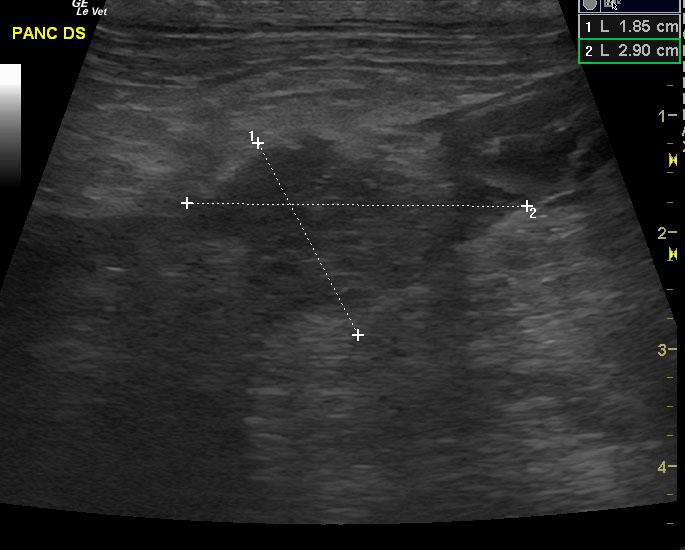

An 11-year-old MN Yorkshire Terrier was presented for intermittent vomiting. Blood work revealed elevated WBC, elevated amylase, elevated lipase, and increased SAP. The patient is anorexic and dehydrated.

Extensive mixed hypoechoic pancreatic parenchyma is noted much of which lacks blood flow on power Doppler assessment. Gastroduodenal thickening is noted with duodenal spasm. Cavitations are noted in the pancreas with echogenic fluid. Extensive hyperechoic fat is noted.

Pancreatic necrosis.

FNA revealed necrosis.